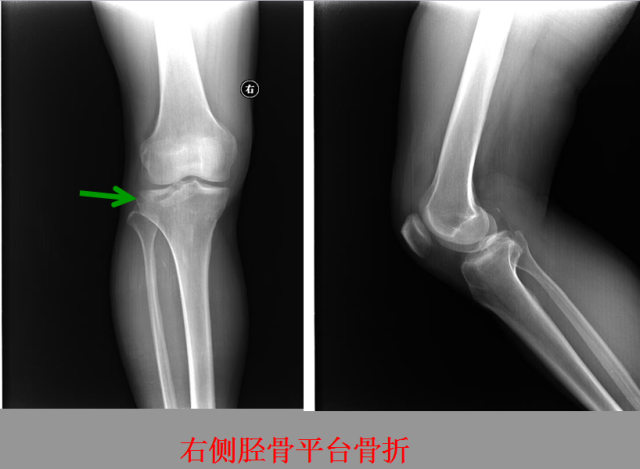

骨折篇

定义:骨折{Fracture}是指骨的完整性和连续性的折裂或粉碎。包括创伤性骨折、疲劳性骨折和病例理性骨折。 临床上以创伤性骨折*常见。